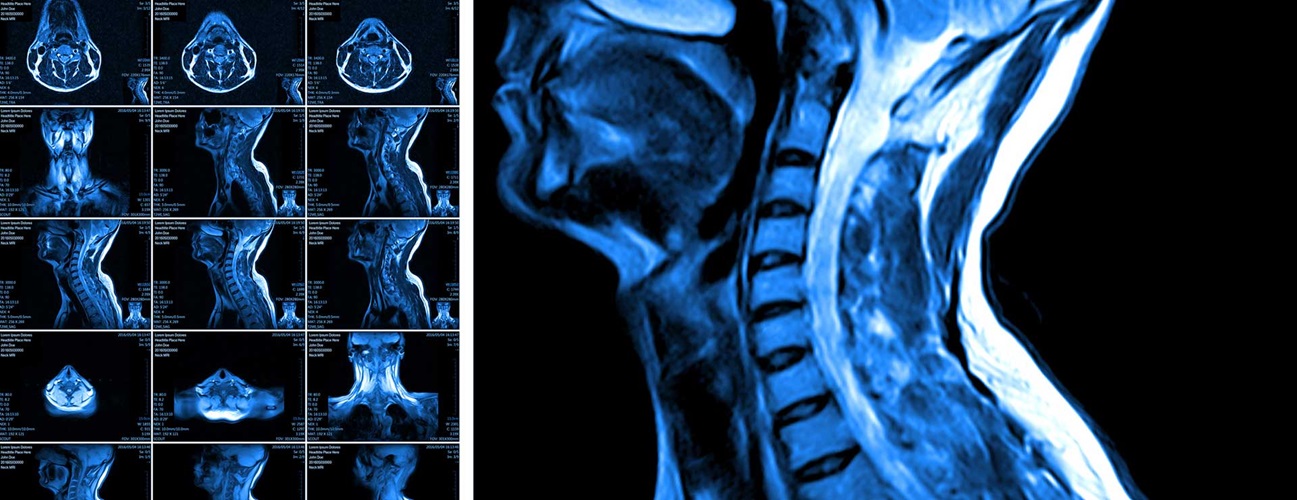

Diagnosing compressive myelopathy involves a combination of clinical evaluation and imaging studies. A thorough neurological examination can identify deficits and help localize the level of compression. Imaging studies, particularly magnetic resonance imaging (MRI), are crucial in visualizing the spinal cord, identifying the source of compression, and assessing its severity. Computed tomography (CT) scans and X-rays may also be used to evaluate bony structures and traumatic injuries.